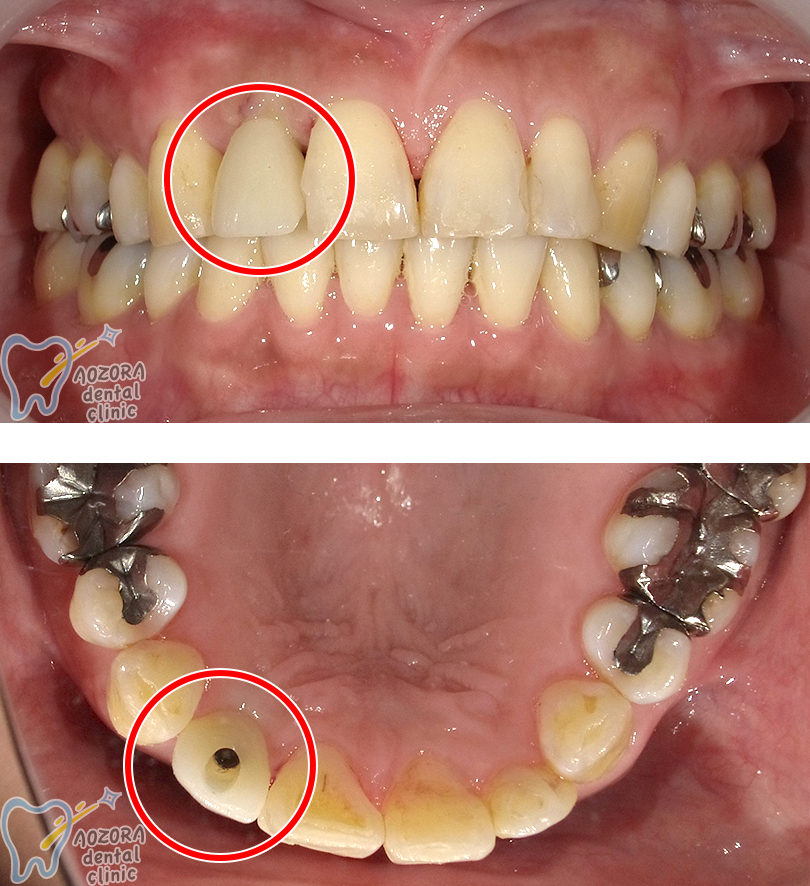

70歳 女性の場合

主訴

歯が折れて、残せなくなったため、インプラントを希望しました。

治療期間 6ヶ月

歯を抜いてから、骨ができるのに3ヶ月

それからOPEをしたため、約6ヶ月かかりました。

術前

術後